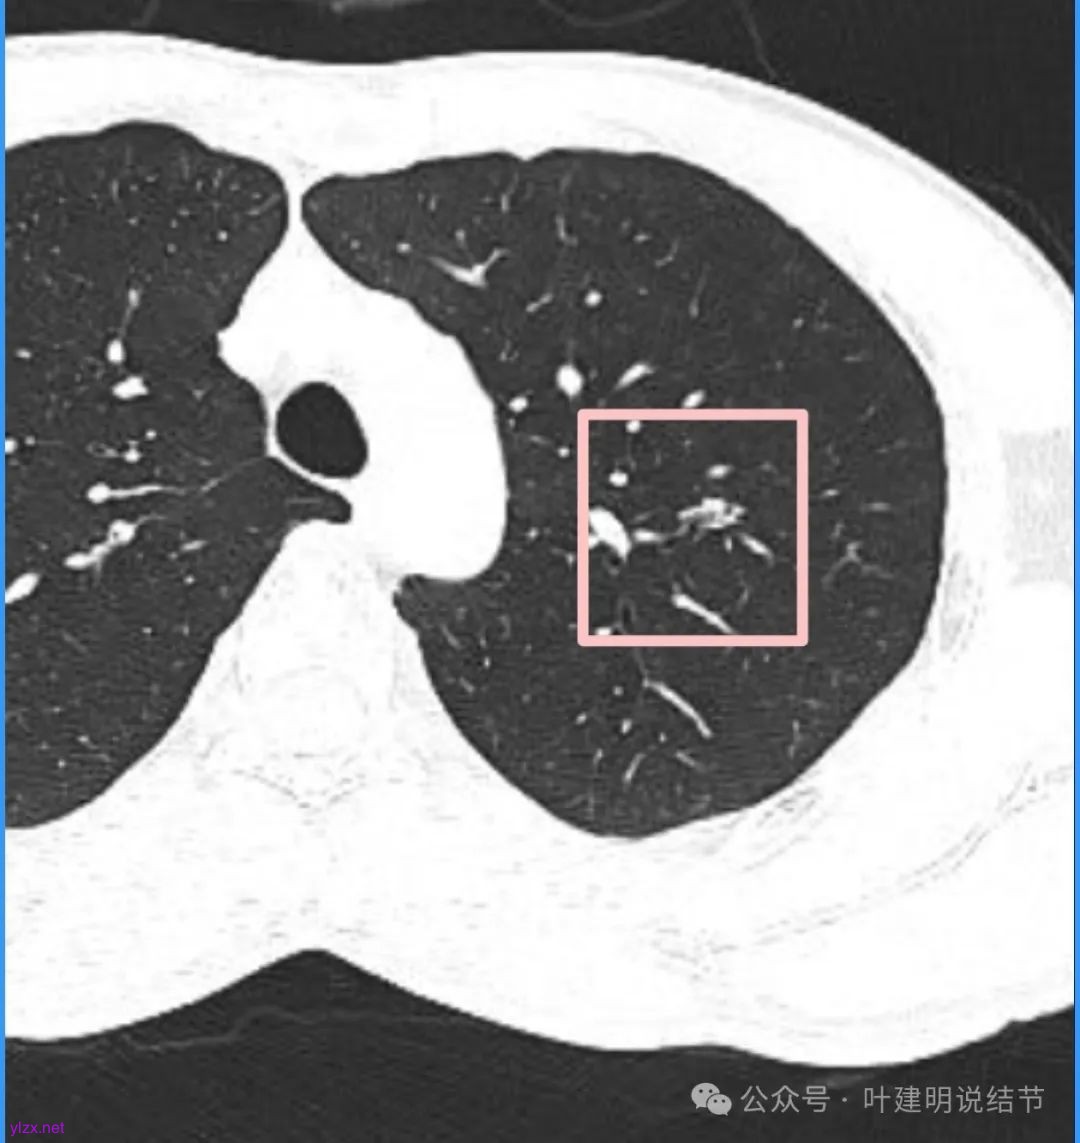

我们先来看2025年3月时的影像:

病灶密度不均,混合密度的样子,相应的细支气管有扭曲略显扩张。

边缘较为毛糙不平,灶内密度杂乱,细支气管穿行,整体轮廓较清。

邻近血管受结节影响,略向病灶侧弯,病灶处是扩张的细支气管还是灶内的空泡征?

有血管征,整体轮廓与边界较清,灶内有蜂窝状。

血管穿过病灶,灶内多个小空泡,整体轮廓较清。